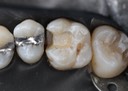

Joe Cha #20 pre-op